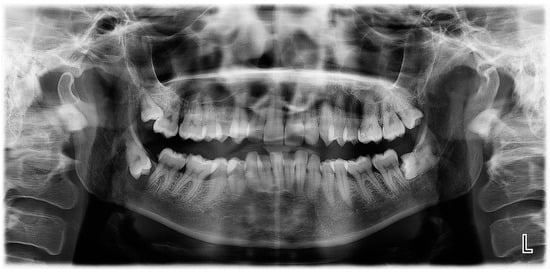

On an OPG X-ray, teeth #38 and 48 were impacted and distally orientated (Figure 10). Tooth #38 showed a radiotransparent lesion measuring 20 × 15 mm, with a well-defined border, multilocular appearance, and a thin septum, most compatible with a DC versus ameloblastoma versus odontogenic keratocyst.

Figure 10.

OPG X-ray of case #4.

On CBCT X-ray, the distal root of the impacted tooth #38 was in contact with the upper wall of the left IAC, generating a discreet deformation of the canal (Figure 11). The cyst showing a multilocular aspect was located adjacent to the crown of tooth #38 and seemed to be attached to the tooth neck. The lesion extending slightly to the ascending branch of the mandible measured 17 mm in height, 21 mm in length and 10 mm in width. In its caudal part, the lesion was in contact with the upper wall of the IAC over about 13 mm. The wall was thinned but with little impact on its internal diameter. The vestibular and lingual cortex were also strongly thinned focally. There was no periosteal reaction or fracture at the mandibular angle. On the bases of these radiological findings, the differential diagnosis included DC, ameloblastoma, and odontogenic keratocyst.

Figure 11.

CBCT X-ray of case #4.